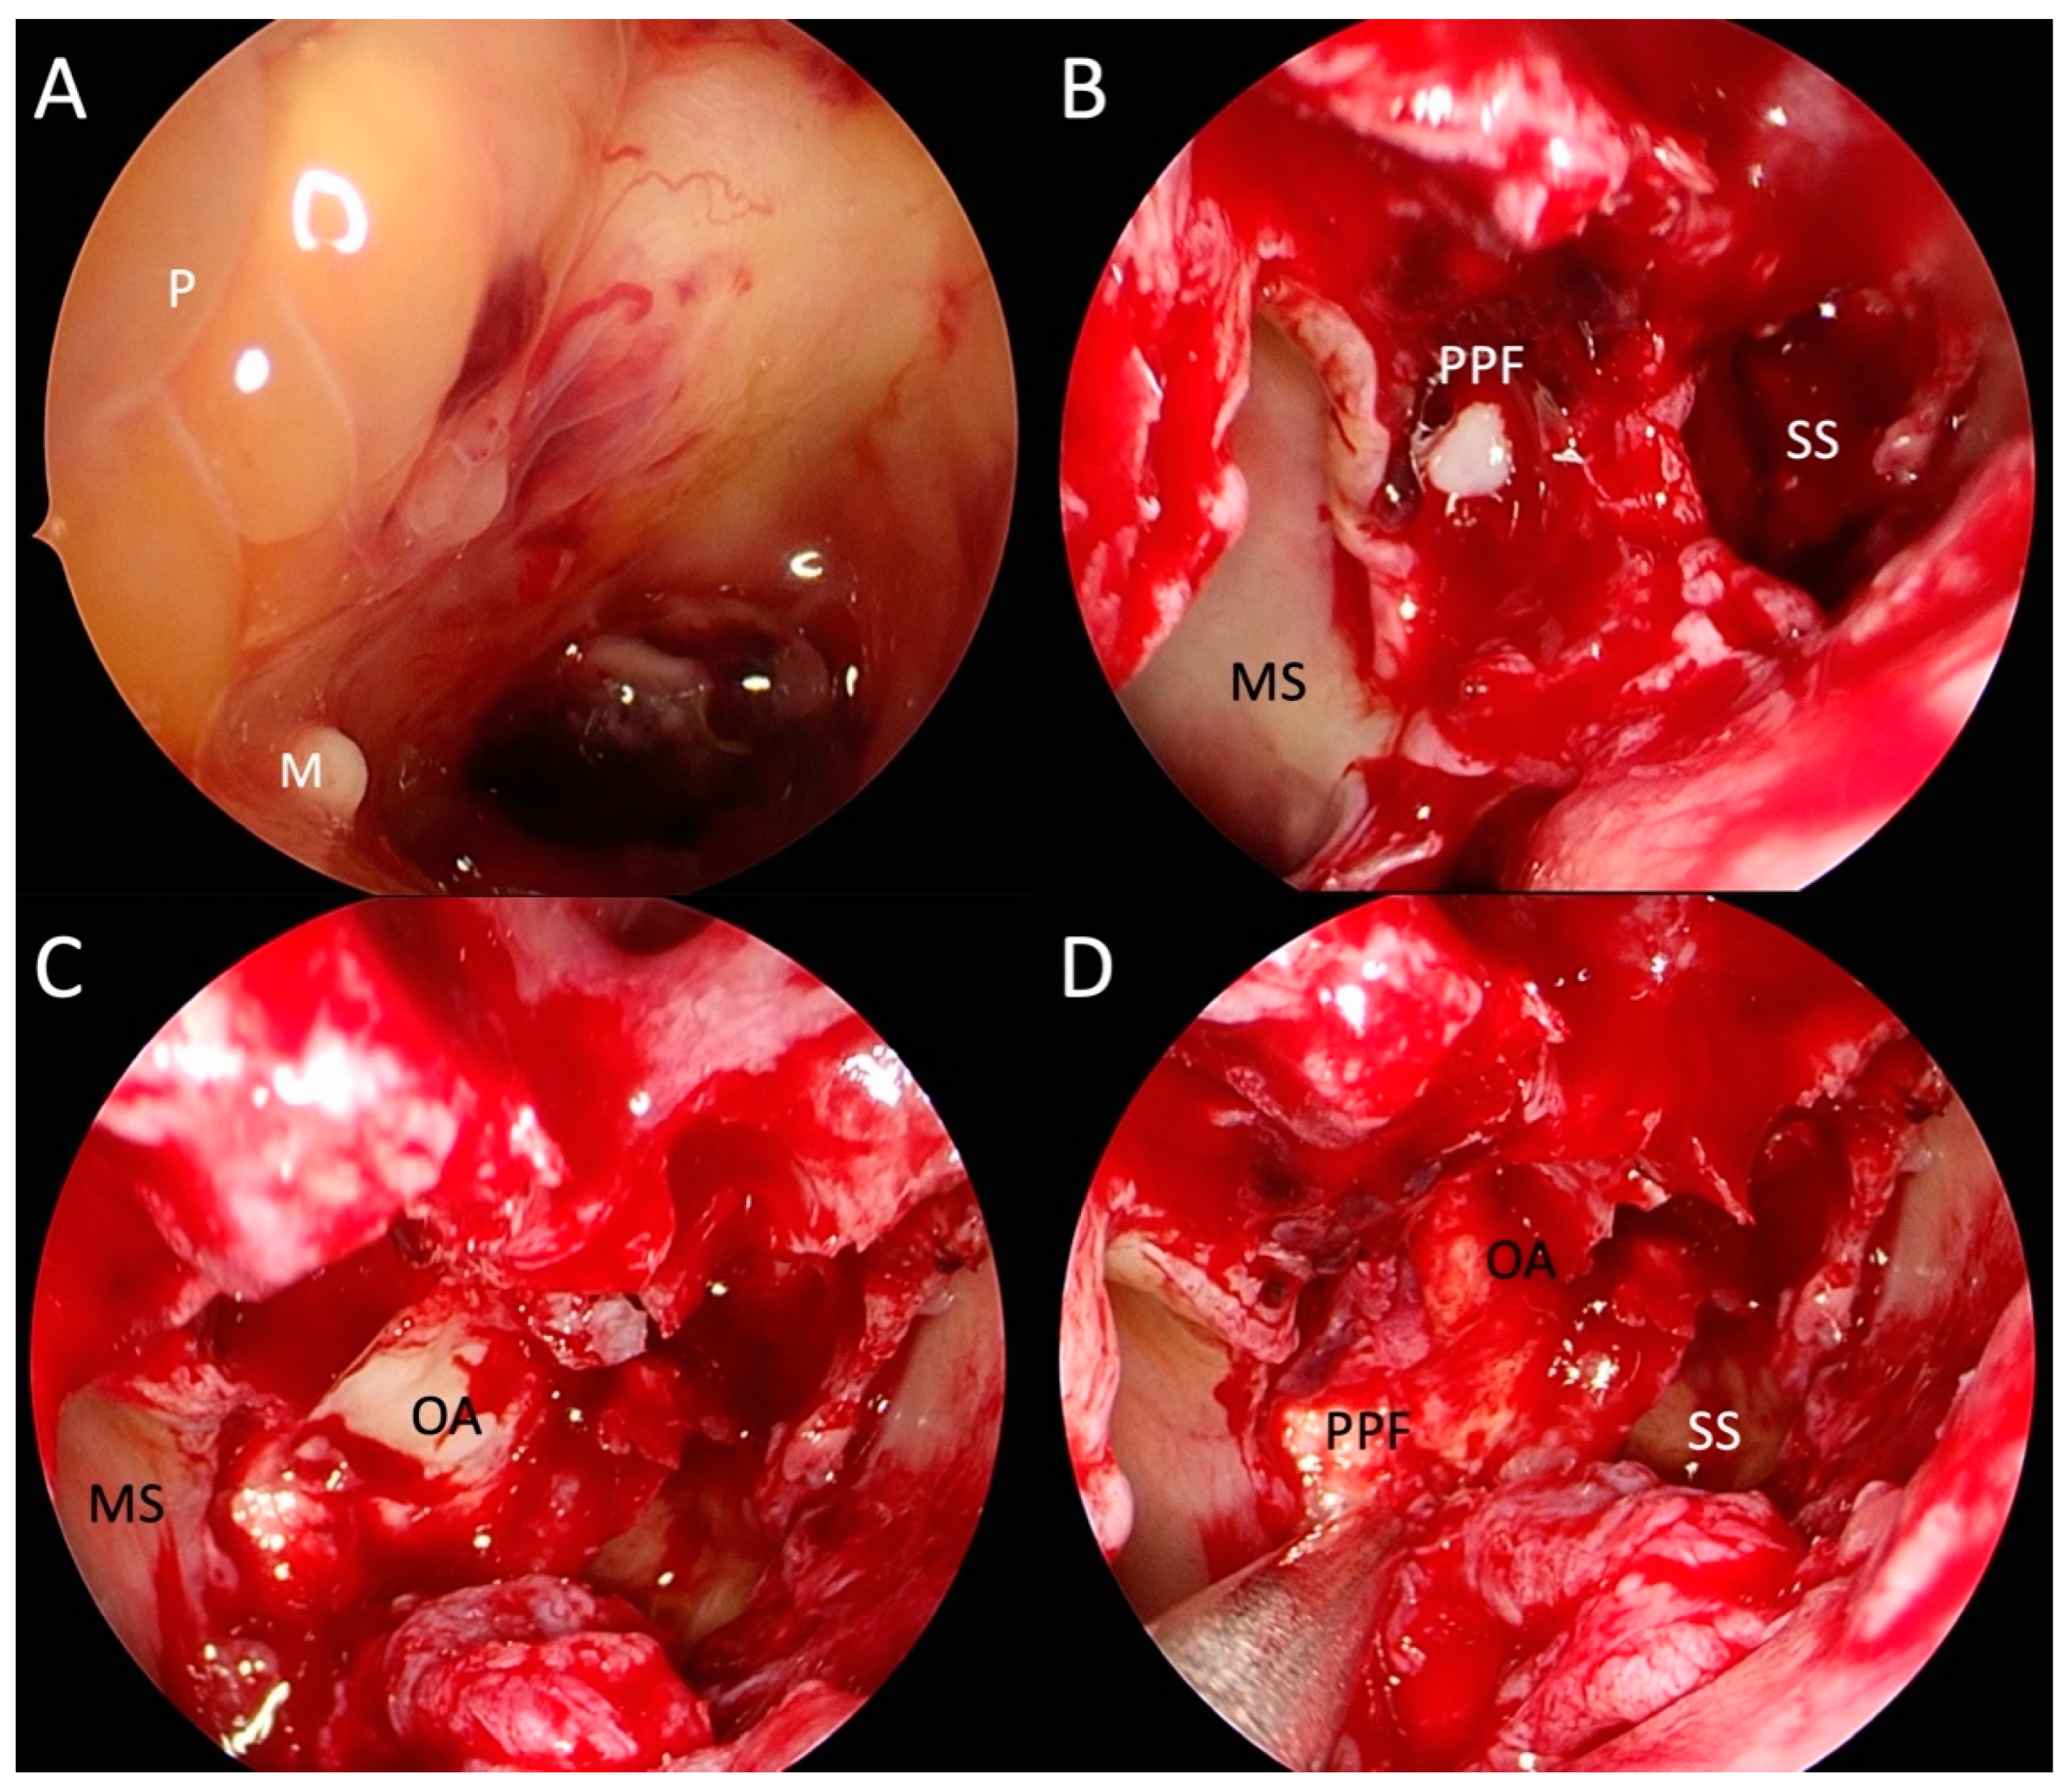

2.2. Revisional Treatment